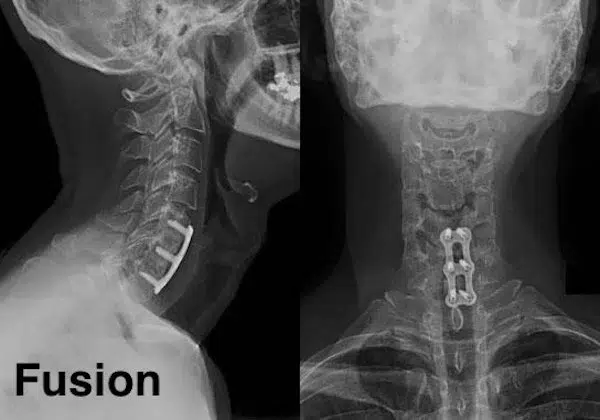

Рентген шейных позвонков при спина бифида

Раздел: Фотозарисовки